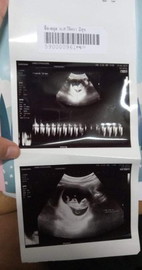

ได้เห็นเด็กน้อยดิ้นตอนยุในท้องรุ้สึกดีใจมากมีโบกมือให้คุนหมอให้ความร่วมมือมากลูก11week3day

เข้าใจความรู้สึกคุณแม่เลยค่ะ ลูกชายในท้องก็โบกมือให้เหมือนกัน แม่ยิ่งหัวเราะ ลูกยิ่งโบก เราถ่ายมาเป็นวีดีโอไว้ ดูทีไร ชื่นใจทุกทีค่ะ